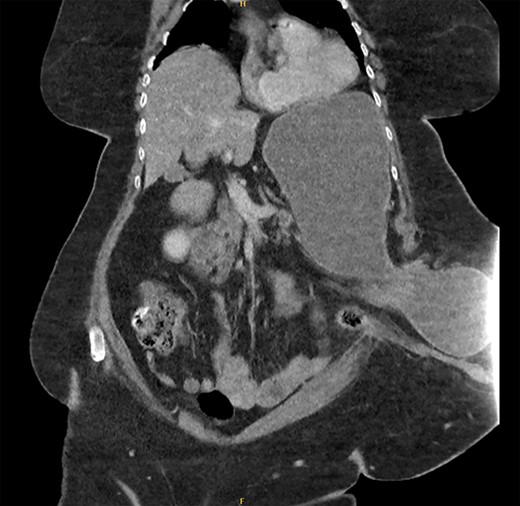

The patient underwent a CT abdomen pelvis (Figs 1 and 2), which reported bowel obstruction secondary to a parastomal hernia on the left containing a large portion of the stomach’s body and antrum.

CT abdomen pelvis—coronal view of parastomal hernia containing stomach.